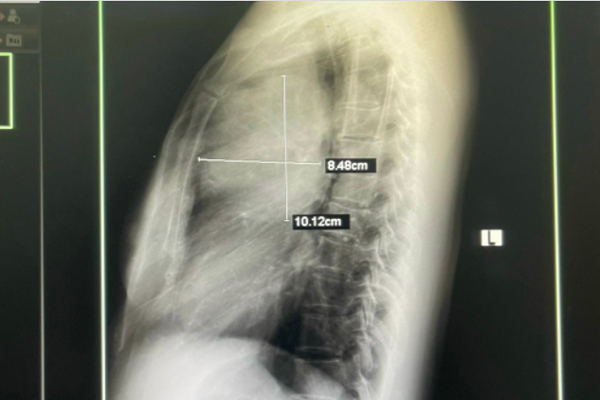

Sau khi được các bác sĩ thăm khám và chỉ định cận lâm sàng, kết quả hình ảnh chụp X-quang tim phổi cho thấy người bệnh có khối u phổi trái, kích thước 8,48cm x 10,12cm. Ngay lập tức, người bệnh được các bác sĩ tư vấn chuyển lên tuyến trên thực hiện các kỹ thuật chẩn đoán chuyên sâu. Kết quả bác sĩ chẩn đoán anh H. mắc ung thư phổi.

Khối u phổi kích thước lớn được phát hiện sau khi chụp X-quang. Ảnh: BVCC